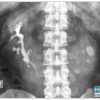

IV. Chẩn đoán x-quang

– Trong trường hợp điển hình thấy hình ảnh bóng 2 thận xoay trục với cực dưới hướng vào trong phía cột sống, gần nhau, cực trên xa nhau.

=> Case lâm sàng 1: